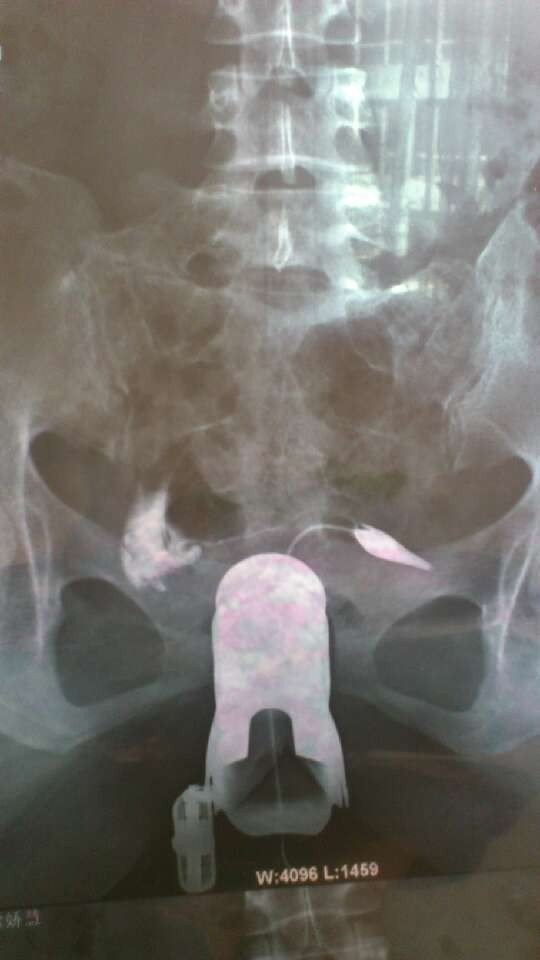

输卵管一侧堵塞,一侧通而不畅,该怎么治疗呢?是该做腹腔镜了,还是再做次造影看看呢? 点击展开 匿名用户 2013-03-20 14:33 为您推荐: 其他回答 还是用中医治疗效果好,恢复输卵管功能 。恢复蠕动,正常怀孕 匿名用户 2013-03-22 13:38 看看能不能做导丝治疗呢 匿名用户 2013-03-20 15:26 相关问题 输卵管造影 医生说 通而不畅 有粘连 建议做腹腔镜 我刚做了妇科检查,有一侧输卵管堵塞,一侧通而不畅,医生建议我做腹腔镜,但我不想做,还有什么好办法吗 今年10月份做了造影左侧输卵管通而不畅右侧不通,医生说做腹腔镜,做腹腔镜能一次通吗?大概要多少钱需…